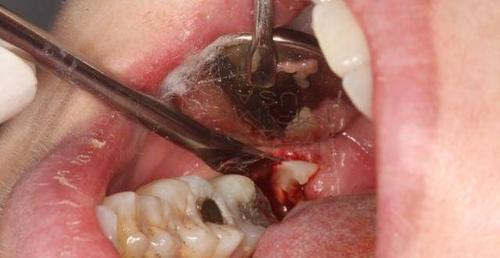

阻生智齿不拔会变得怎么样?

智齿怎么拔的过程图解

阻生智齿图片